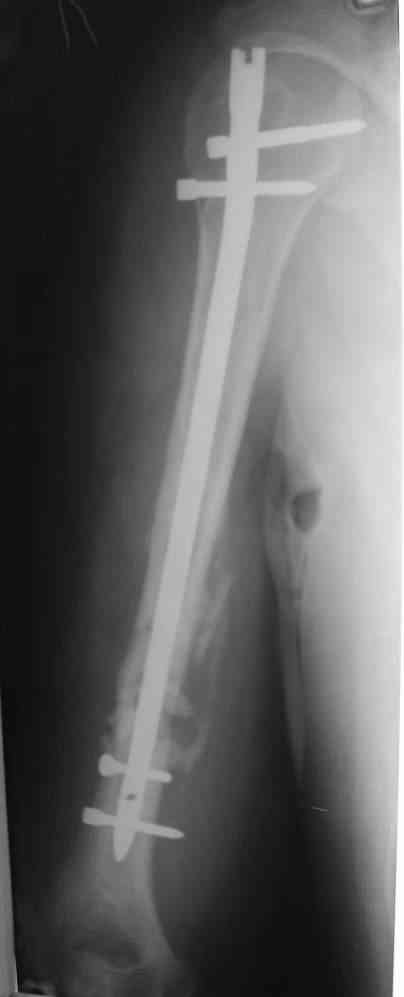

Уважаемые коллеги! Помогите в выборе тактики лечения больной Р.,56 лет, с болтающимся ложным суставом с/3 правой плечевой кости 2-х летней давности. В анамнезе - бронхиальная астма, гормонозависимая форма, ожирение III cт. Травма - автодорожная, получила закрытый многооскольчатый перелом диафиза плечевой кости со смещением (от метафиза до метафиза), в экстренном порядке нами произведен закрытый остеосинтез стержневым аппаратом, отломки удалось сопоставить анатомически. В дальнейшем больная выпала из поля зрения. Как потом выяснилось, после снятия стержневого аппарата, больная долечивалась по Илизарову специалистом из г. Кургана. Аппарат Илизарова удален из-за нагноения мягких тканей. Последние два года работая бухгалтером, фиксирует плечо ортезом. Теперь вновь обратилась к нам для ликвидации ложного сустава.

На мой взгляд, целесообразно выполнить антеградный блокируемый интрамедуллярный остеосинтез. При наличии достаточного диаметра костномозгового канала по проводнику произвести его рассверливание и установить штифт по-возможности без вскрытия места перелома. При наличии симптомов повреждения лучевого нерва необходимо выполнить его ревизию и мобилизовать отломки "открыто".

Предложение коллеги Мамонова, возможно, более привлекательно. У пациентов с невысокими функциональными потребностями есть смысл добиваться не сращения, а стабильной, безболезненной и функциональной конечности, что может быть достигнуто "эндопротезированием диафиза" интрамедуллярным стержнем. У нас несколько таких больных наблюдаются уже 2-3 года, вроде неплохо.

Будут трудности с закрытым вскрытием канала (нужен инструмент типа длинного шила). Можно взять штифт с блокированием, а можно и прямоуголного сечения типа Зверева-Ключевского. Есть варианты закрытого штифтования в нейтральном положении, с компрессией, открыто с резекцией и компрессией.

Мы бы предложили БИОС ретроградно (хотя это не принципиально, можно и сверху). Учитывая,что ложняк "болтающияся", больших трудностей с закрытым вскрытием канала (в зоне ложного сустава) быть не должно. Конечно нужен инструмент: сначала длинная (350-400 мм) острая спица (шило)диаметром 4-5 мм., затем гибкие развертки до 8-9 мм и соответствующий массивный штифт...

Штифт - отвисание проксимального отдела - накостный остеосинтез, нагноение, АФВ с ревизиями раны, опять пластина и снова нестабильность. Была удалена пластина и выполнен БИОС штифтом ChM (ДЕОСТ). Через 2 нед. пациент сел за руль и вышел на работу. Причем так и работает до сих пор уже 1,5 года, хотя полного сращения мы вроде бы не достигли ( снимки пришлю позже) - пациент не приходил на осмотры, общался только по телефону.

Второй пациент перенес два неудачных накостных остеосинтеза на фоне пареза лучевого нерва. Была удалена пластина и выполнен БИОС штифтом ChM (ДЕОСТ) - это была наша первая операция БИОС.